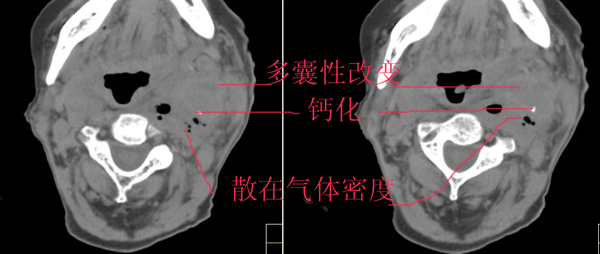

除上诉考虑外,那么多而且不规则、不定形的钙化还应该想到有颈部畸胎瘤的可能性。顺着思路继续,颈部畸胎瘤继发产气菌感染,并在颈总动脉局部形成小脓肿且浸蚀到血管壁。

左颈部血管增粗,周围软组织肿胀模糊,内有蜂窝状积气影,左侧甲状腺增大,气管受压右移,气管软骨环未受侵。结合病史较短考虑:左颈部脓肿破裂并血管瘤形成,左甲状腺瘤。

考虑血管破裂没什么问题,但颈部这么多积气哪来的?有外伤吗?或颈部脓肿腐蚀血管?